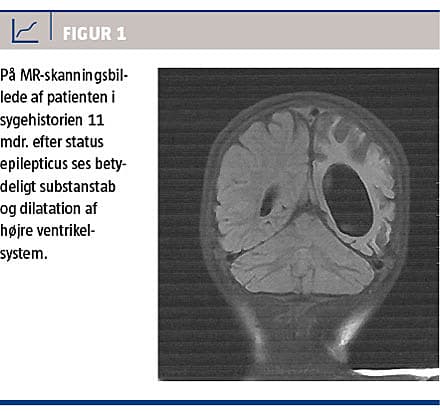

Ved opfølgning knap et år senere var hun ikke alderssvarende udviklet. Hun havde en højresidig parese med øget tonus, daglige epileptiske anfald og fremtrådte sprogligt og kognitivt som en toårig (biologisk alder knap fire år). En MR-skanning 11 måneder efter SE viste tilkommet betydeligt substanstab med let midtlinjeforskydning og dilatation af højre ventrikelsystem (Figur 1).

Perfussionsstudierne viste normale forhold i cerebellum og højre hemisfære og nedsat perfusion i hele venstre hemisfære.